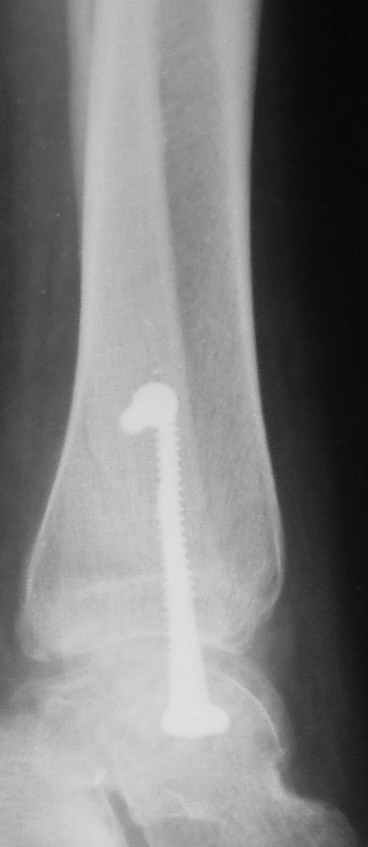

Ниже рентгенограммы

До операции 28 июля